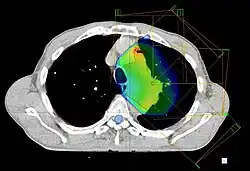

Przykładowy układ wiązek promieniowania w Radioterapii nowotworu płuca

Przekrój z badania (tomografi komputerowej) CT z dawką promieniowania, przykładowy układ wiązek promieniowania w radioterapii nowotworu płuca